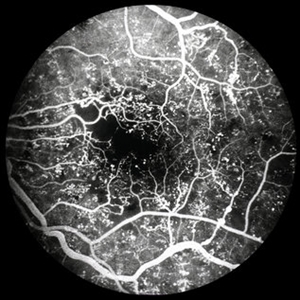

PDR with Severe Macular Ischemia

PDR with severe macular ischemia, FA, early phase.

Condition/keywords: early phase, macular ischemia